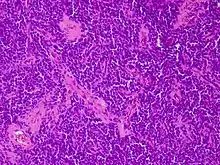

| Micrograph of an H&E stained section of a peripheral PNET. | |

"Current evidence indicates that both Ewing's sarcoma and PNET have a similar neural phenotype and, because they share an identical chromosome translocation, they should be viewed as the same tumor, differing only in their degree of neural differentiation. Tumors that demonstrate neural differentiation by light microscopy, immunohistochemistry, or electron microscopy have been traditionally labeled PNETs, and those that are undifferentiated by these analyses have been diagnosed as Ewing's sarcoma."[5]